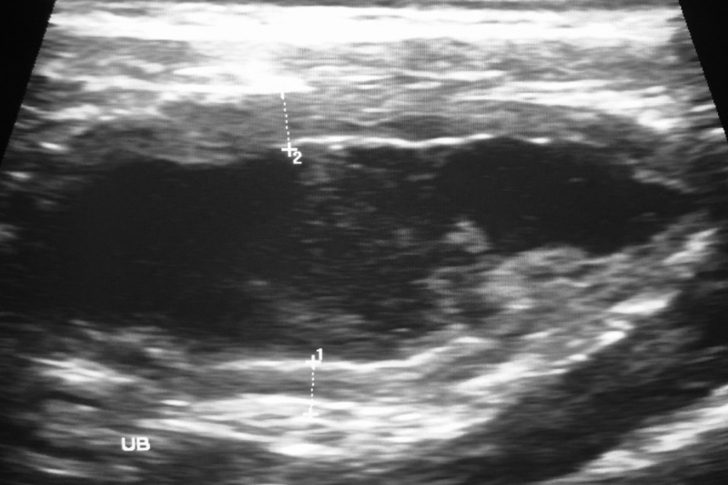

Polizei und Ultraschall

Es verging nur wenig Zeit, in der die Ärztin das Tier untersuchte, währenddessen traf die Polizei ein. Die Ranger trauten ihren Augen nicht, als sie die Beamten sahen, was hatten sie hier zu suchen? Es stellte sich heraus, dass die Tierärztin die Behörden benachrichtigt hatte, nachdem sich ihr schrecklicher Verdacht bestätigt hatte.

Nach kurzen Vital-Checks hatte sie den Bauch des Löwen mit einem Ultraschallgerät untersucht und gefunden, wonach sie gesucht hatte.

Fremdkörper im Magen

Der Mageneingang des Tieres war blockiert, der Löwe hatte definitiv etwas gefressen, dass er selbstständig weder verdauen, noch ausscheiden konnte. Die Folge waren die enormen Schmerzen und dass sich der Bauch immer weiter aufblähte. Wenn die Ärztin jetzt nicht handelte, würde der Löwe qualvoll an inneren Verletzungen sterben, es gab nur noch eine Möglichkeit, wie die Ärztin den großen Vierbeiner retten könnte.